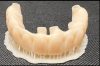

(14.) Examples of the different types of fixed full arch prostheses described by the Misch classification system, including an FP1 crown only restoration, an FP2 “long teeth” restoration, and an FP3 restoration that incorporates a pink component, respectively.

Figure 14

(15.) Examples of the different types of fixed full arch prostheses described by the Misch classification system, including an FP1 crown only restoration, an FP2 “long teeth” restoration, and an FP3 restoration that incorporates a pink component, respectively.

Figure 15

(16.) Examples of the different types of fixed full arch prostheses described by the Misch classification system, including an FP1 crown only restoration, an FP2 “long teeth” restoration, and an FP3 restoration that incorporates a pink component, respectively.

Figure 16

When a fixed prosthesis is desired, the decision regarding what type warrants careful consideration. The Misch system classifies fixed full-arch prostheses into three categories: FP1, FP2, and FP3.11 FP1 denotes a fixed prosthesis that replaces only the crown forms of missing teeth with no pink material to replace the gingiva. This type of prosthesis is indicated for edentulous arches that demonstrate minimal loss of hard and soft tissue (Figure 14). FP1 prostheses include bridges where artificial teeth are supported by natural teeth or implants. In contrast, FP2 prostheses replace the anatomical crown and root forms of missing teeth (Figure 15). These are intended to address edentulous arches with minimal to moderate loss of hard and soft tissue. And finally, FP3 protheses replace the anatomical crown and a portion of the soft tissue, incorporating pink material to restore the full complement of teeth and gingival tissues for arches that demonstrate a moderate to advanced loss of hard and soft tissue (Figure 16). Each option presents distinct benefits and considerations regarding function, esthetics, health, and long-term maintenance. By carefully assessing these factors, dental professionals can customize treatment plans to accommodate the individual needs and preferences of all patients. For example, addressing a smile that exhibits vertical maxillary excess may require extensive bone reduction to conceal the transition zone of an FP3 prosthesis, whereas an FP1 solution may require no or only minor bone removal, which may be more suitable for the patient and clinician.